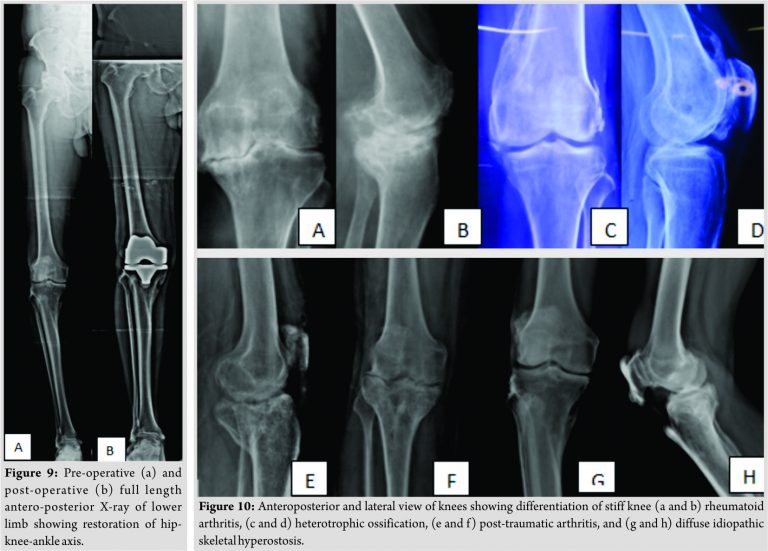

Resecting 4 more mm of bone from the femur and the tibia was an unusual and surprising phenomenon of this surgical reconstruction as deformity was not significant. Knee replacement was done by the cemented posterior stabilized system (Legion®, Smith and Nephew, Memphis [TN], USA). The coronal femoral angle was corrected from 86.4° to 90.1° and the coronal tibial angle corrected from 85° to 89.5° postoperatively (Fig. 8). The Hip-Knee-Ankle (HKA) angle improved from 170.5° to179.6° postoperatively (Fig. 9). His knee society score improved from 34 points to 85 points, postoperatively. The functional score improved from 19 points to 80 points. Joint line elevation can be seen in comparative pre-operative and post-operative X-rays. 75 mg indomethacin was given daily for 6 weeks as prophylaxis for heterotopic calcification [11]. At final follow follow-up of one 1 year,the patient had 5 degree flexion deformity and up to 95° degree range of motion. Usually 5° flexion deformity resolves with rehabilitation, but in this case, it was resistant, which can be explained by the inability of soft tissues to stretch and accommodate to the prosthetic implants.

The main objective of this case report is to clearly delineate the clinical and radiological features of DISH at the knee joint and outline the principles and important steps to perform total knee arthroplasty (TKA) in case of DISH. DISH at knee joint should be differentiated from other causes of the stiff knee like such as inflammatory arthropathy, heterotrophic ossification, and post-traumatic arthrosis (Fig. 10). Inflammatory arthropathies have a female preponderance and are associated with synovial proliferation and regional osteopenia [12]. Upto 2 mm additional bone resection along with posterior soft tissue release usually corrects the flexion deformity associated with rheumatoid arthritis. These features should be differentiated from post head injury, or post-burn heterotrophic ossification where these are periarticular bony bridges across the joint unlike DISH where their ossification is in the soft tissues [13]. In post-traumatic arthrosis, implants and associated fibrosis may be the cause of stiffness and navigation may help in by passing the implant and perform TKA without the need to remove the implants [14]. DISH can be differentiated from other causes of stiffness by calcification in the supra and infrapatellar part of quadriceps expansion. There is ossification along with the collateral ligaments and spurring at the tibial insertion of the patellar tendon. Once the diagnosis of DISH is made at the knee, certain measures need to be followed to perform a successful TKA. DISH knee can be resistant to correction because of due to unyielding soft tissues. Upto 8 mm more bone, 4 mm each from femur and tibia may be required to be cut to achieve successful prosthetic implantation. This will elevate the joint line and cause patella baja and patellar maltracking [15]. In this case, the patellar button was superiorized and medialized to optimize patellar tracking. Moreover, a complete lateral release had to be performed because the ossification in quadriceps tendon and lateral retinaculum was causing lateral subluxation of the patella. Apart from +4mm of distal femur resection, posterior capsule was completely elevated from the posterior aspect of the femur to increase the extension space. Furthermore, postero-medial capsule was cut in extension with a laminar spreader in the extension space. All these measures helped to achieve extension of the knee up to 5°. The final arc of movement as shown by navigation was 5–95° flexion. To improve the flexion of the knee pie crusting of quadriceps tendon was done but the flexion was resistant to improvement. After all the measures, the final arc remained 5–95°. Supervised rehabilitation was advice to the patient but at one 1 year follow follow-up, the arc of knee motion remained unchanged from 5 to -95°. This is unusual as 5° flexion deformity usually resolves with physiotherapy but did not in this case because of due to periarticular and ligamentous ossification. Patient undergoing TKA for Diffuse Idiopathic Skeletal Hyperostosis should be prognosticated regarding possibility of decreased range of motion postoperatively as the soft tissue envelope loses its elasticity and ability to stretch because of enthesetic ossification. While performing knee replacement for DISH cautious prognostication should be done to the patient regarding possibility of decreased flexion after arthroplasty as the soft tissue envelope loses its elasticity and ability to stretch because of enthesetic ossification. Current controversies and future considerations: Little is known about the etio-pathogenesis, genetic basis, therapeutic approach, progression of spinal, and extra-spinal manifestation of DISH. Furthermore, the classification system tends to classify the disease at a later stage, hence making it difficult for any therapeutic modality to influence the progression of the disease. Current efforts and researches are directed towards finding a genetic link to DISH, developing a new classification to identify the patients at an early stage and development of novel targeted therapies.